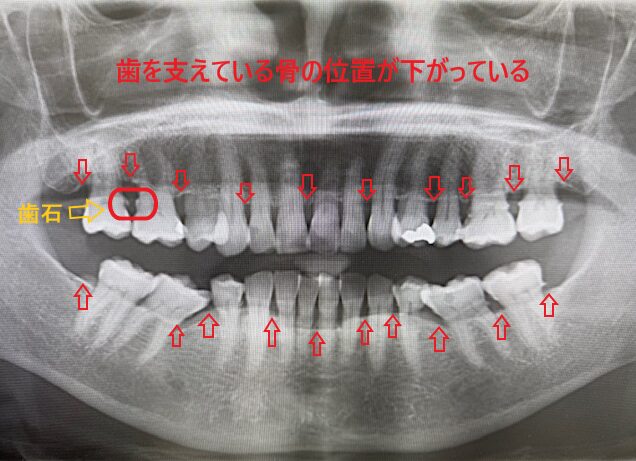

《歯周病の骨の位置のレントゲン》